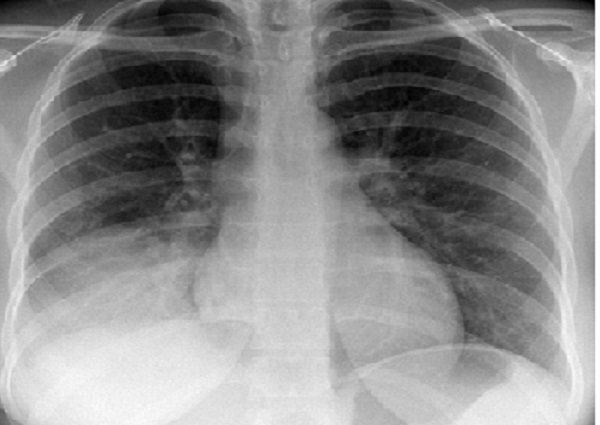

Hội chứng đông đặc phổi là một bệnh lý của nhu mô phổi có thể được phát hiện thông qua các phương pháp lâm sàng và hình ảnh chụp X-quang. Có rất nhiều nguyên nhân có thể dẫn đến tình trạng bệnh này, do đó việc chẩn đoán bệnh yêu cầu sự kết hợp giữa việc thăm khám lâm sàng và thực hiện các xét nghiệm cận lâm sàng. Bài viết dưới đây sẽ giới thiệu cho bạn đọc những thông tin cơ bản nhất về hội chứng đông đặc phổi.

Hội chứng đông đặc phổi là hiện tượng không khí trong các đường dẫn khí nhỏ của phổi bị thay thế bằng thứ khác như mủ, máu hay thức ăn trong dạ dày. Đây là một tình trạng y tế nghiêm trọng và tiềm ẩn nguy hiểm cho sức khỏe của người bệnh. Hiểu đơn giản, hội chứng đông đặc phổi là tình trạng mà các động mạch phổi bị tắc nghẽn do đông máu hoặc cặn bã trong hệ thống tuần hoàn. Tình trạng này có thể gây ra các biến chứng nguy hiểm như đột quỵ phổi và tử vong nếu không được phát hiện và điều trị kịp thời.

Triệu chứng lâm sàng và hình ảnh phổi trên phim chụp X-quang gần như tương tự giữa các nguyên do khác nhau. Do đó, thường thì bạn sẽ cần nhiều xét nghiệm hơn để xác định nguyên nhân cụ thể gây ra tình trạng đông đặc trong phổi của bạn.